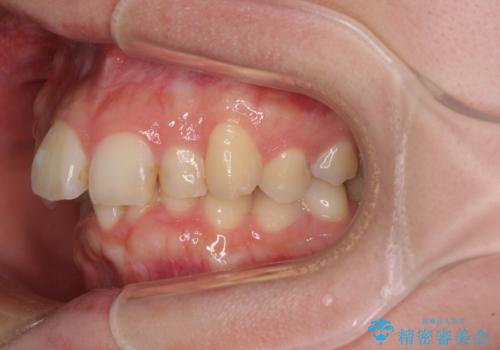

- 前歯のデコボコを気にして来院された患者様です。

上下の前歯にデコボコがあり、更にはディープバイトにより下顎前歯の大半が隠れている状態でした。

上顎左右第一小臼歯の2本を抜歯し、ワイヤー装置を使用して咬み合わせ高さを改善しながら、歯列を整えて行くこととしました。

事前にむし歯の疑いがある歯があり、処置を行いましたが、矯正治療中に失活してしまい、ワイヤー装置除去後に、根管治療とセラミッククラウンによる補綴治療を行いました。

矯正治療は2年半ほで無事におけることができました。